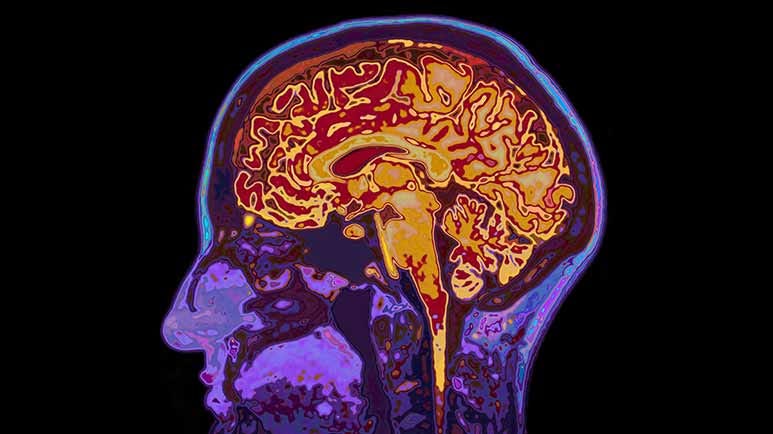

A theory on how IBD affects cognitive function — The study points to several interconnected processes. Chronic systemic inflammation — a hallmark of IBD — results in high levels of inflammatory cytokines circulating in the bloodstream. These pass through the blood-brain barrier where they disrupt the brain's delicate chemical balance and interfere with neuron-to-neuron communication. Over time, this inflammatory environment contributes to neurodegeneration.

For example, the researchers pointed to gut dysbiosis — an imbalance in the populations of bacteria living in your intestines. In healthy digestion, beneficial bacteria produce short-chain fatty acids (SCFAs), which help regulate inflammation and maintain the blood-brain barrier integrity. In IBD, the balance shifts toward harmful bacteria, reducing these protective compounds.

This imbalance leads to increased intestinal permeability, which allows harmful toxins and bacterial byproducts to enter the bloodstream and reach the brain.

The disruption of the gut-brain axis is another factor — IBD-related changes to gut nerves and immune signaling can alter brain function directly.

Chronic systemic inflammation is a central suspect — Similar to the Scientific Reports study, this research also theorizes that inflammatory cytokines breach the blood-brain barrier. Once inside, they disrupt nerve cell communication, damage neurons, and trigger neurodegeneration linked to dementia.

On a related note, the researchers pointed out the role of gut microbial-derived neurotoxic metabolites, which are harmful byproducts produced by an imbalanced gut microbiome. These byproducts travel through the bloodstream to the brain, where they may interfere with normal brain function and speed up the neurodegenerative processes.